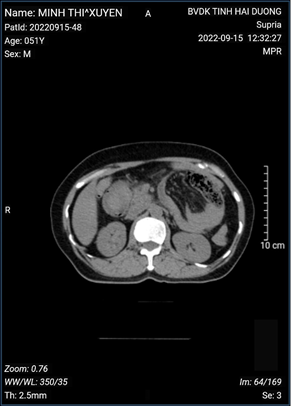

Chụp cắt lớp vi tính ổ bụng: các quai ruột non giãn kèm mức hơi dịch ( hình ảnh tắc ruột)